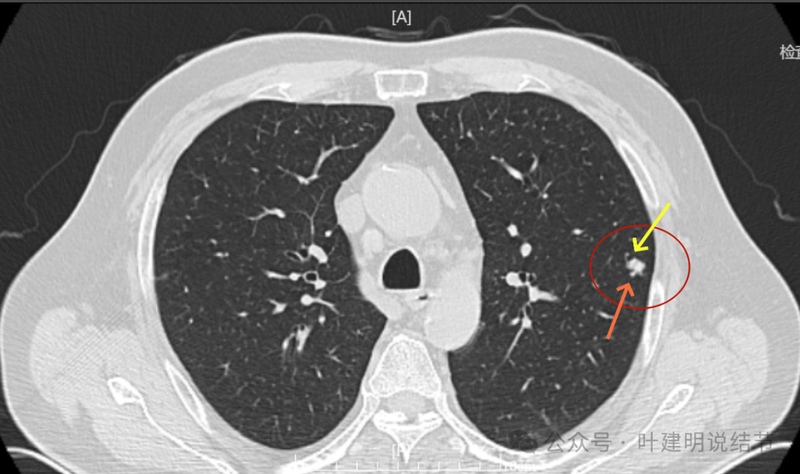

病灶出现,密度较高。

边缘不光滑。

血管与之关系密切,实性密度。

整体有膨胀感,血管有进入病灶。

实性密度并圆形或类圆形,膨胀性明显。

血管进入明显,边缘毛糙不光滑。

血管进入以及表面不平,形态不规则。